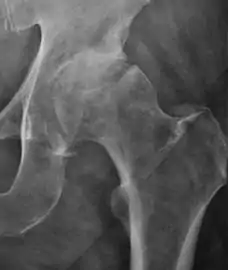

Plain radiography allows us to categorize the hip as normal or dysplastic or with impingement signs (pincer, cam, or a combination of both). Besides these, pathologic processes like osteoarthritis, inflammatory diseases, infection, or tumors can also be identified (Figure 1).[1]

Figure 1.

Osteoarthritis

In adults, one of the main indications for radiographs is the detection of osteoarthritic changes (Figure 1(e)). Nevertheless, radiographs usually detect advanced osteoarthritis that can be graded according to the Tönnis classifications. The grading system ranges from 0 to 3, where 0 shows no sign of osteoarthritis. Intermediate grade 1 shows mild sclerosis of the head and acetabulum, slight joint space narrowing, and marginal osteophyte lipping. Grade 2 presents with small cysts in the femoral head or acetabulum, moderate joint space narrowing, and moderate loss of sphericity of the femoral head. Grade 3 is the severest form of osteoarthritis, which manifests as severe narrowing of the joint space, large subchondral cyst with productive bone changes that may lead to deformity of the bone components of the joint, while secondary osteoarthritis due to calcium pyrophosphate deposition can be diagnosed when calcification of hyaline cartilage and fibrocartilage is detected.[1]

There are other pathological conditions that can affect the hip joint and radiographs help to make the appropriate diagnosis. Acute bacterial septic arthritis can be diagnosed by radiographs when a fast regional osteoporosis and destructive monoarticular process develops (Figure 1(f)). In case of tuberculous or brucella arthritis it is manifested as a slow progressive process, and diagnosis may be delayed.[1]